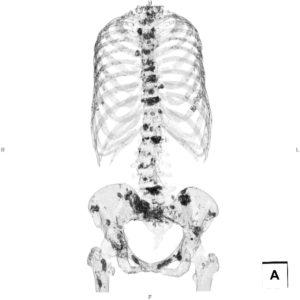

Bone Scintigraphy-Like Image』

造影CT検査の画像処理を工夫することで、骨シンチグラフィーのような画像を作成する「Bone Scintigraphy-Like Image」を提示しました。造影CT検査で、今まで評価が難しかった骨転移を描出する方法として考案しました。実用化し広く普及できるよう、検討を継続していきます。